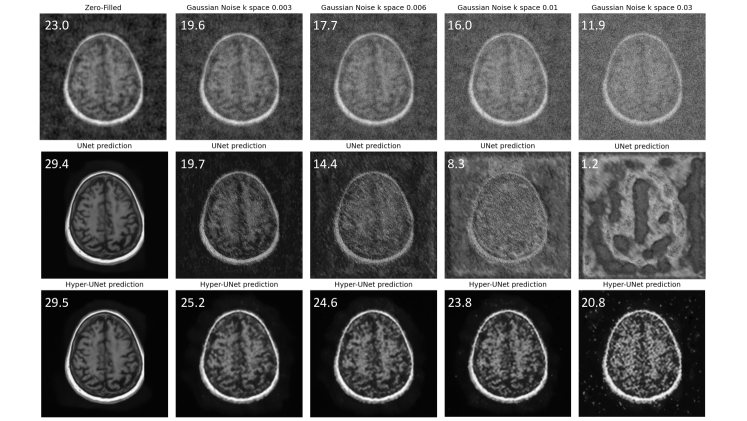

Results: We first demonstrate the superior performance of hyper-convolution with fully-sampled test images. We train 3 Hyper-UNet models with kernels and varying . The corresponding number of parameters for these three models are 2.2M, 1.2M, and 0.73M. Figure 7 shows violin plots for PSNR values. The average PSNR of these three models decrease from 30.4 to 30.16, 29.39, as the number of parameters decreases. The fourth model in Figure 7 is the baseline with regular convolutions and 2.2M parameters. This baseline achieves an average PSNR of 29.36. We keep all other hyper-parameters such as number of channels the same for these four models to achieve a fair comparison. We observe that all hyper-convolution models outperform the baseline. Even the smallest hyper-convolution model obtains a similar PSNR to the baseline, with only 1/3 of the total trainable parameters. We also notice that hyper-convolution models have smaller variation in terms of the individual PSNR among all test images.

We test the robustness of the reconstruction models (trained with clean data), by adding Gaussian noise (with different standard deviation) to the test data333Results shown correspond to adding the noise in k-space. Experiments with image domain noise exhibit same pattern of results and are excluded due to page restrictions. As reference, we show the PSNR for the zero-filled reconstructions, which are provided as input to the models. For a reconstruction network, the objective is to achieve an output PSNR value that is higher than the zero-filled (input) PSNR. We observe that both UNet and hyper-UNet obtain equally high PSNR values for noise-free input images. However, the performance of the UNet baseline quickly drops below the input PSNR as the degree of noise increases, underscoring the vulnerability of regular convolutions to even slight perturbations or corruption. On the other hand, the hyper-UNet yields output PSNR values that stay above the input PSNR, producing improved quality reconstructed images, despite the distribution shift introduced by the additive noise. A qualitative observation from Figure 9 is that the hyper-convolution model can produce useful results, even when the baseline’s output is completely wrong. We believe this type of robustness is critical for the real-world deployment of these models.